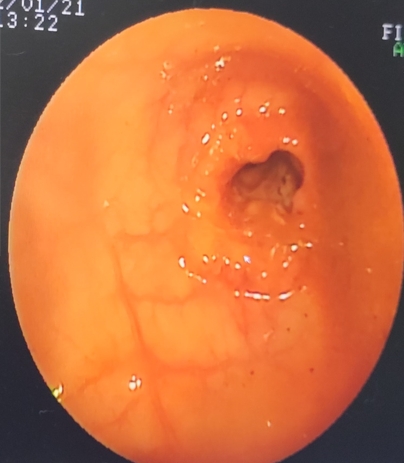

發現結腸黏膜有環狀增生,外形不規則,緊接著就採樣經組織病理醫師診斷為直腸腺癌。